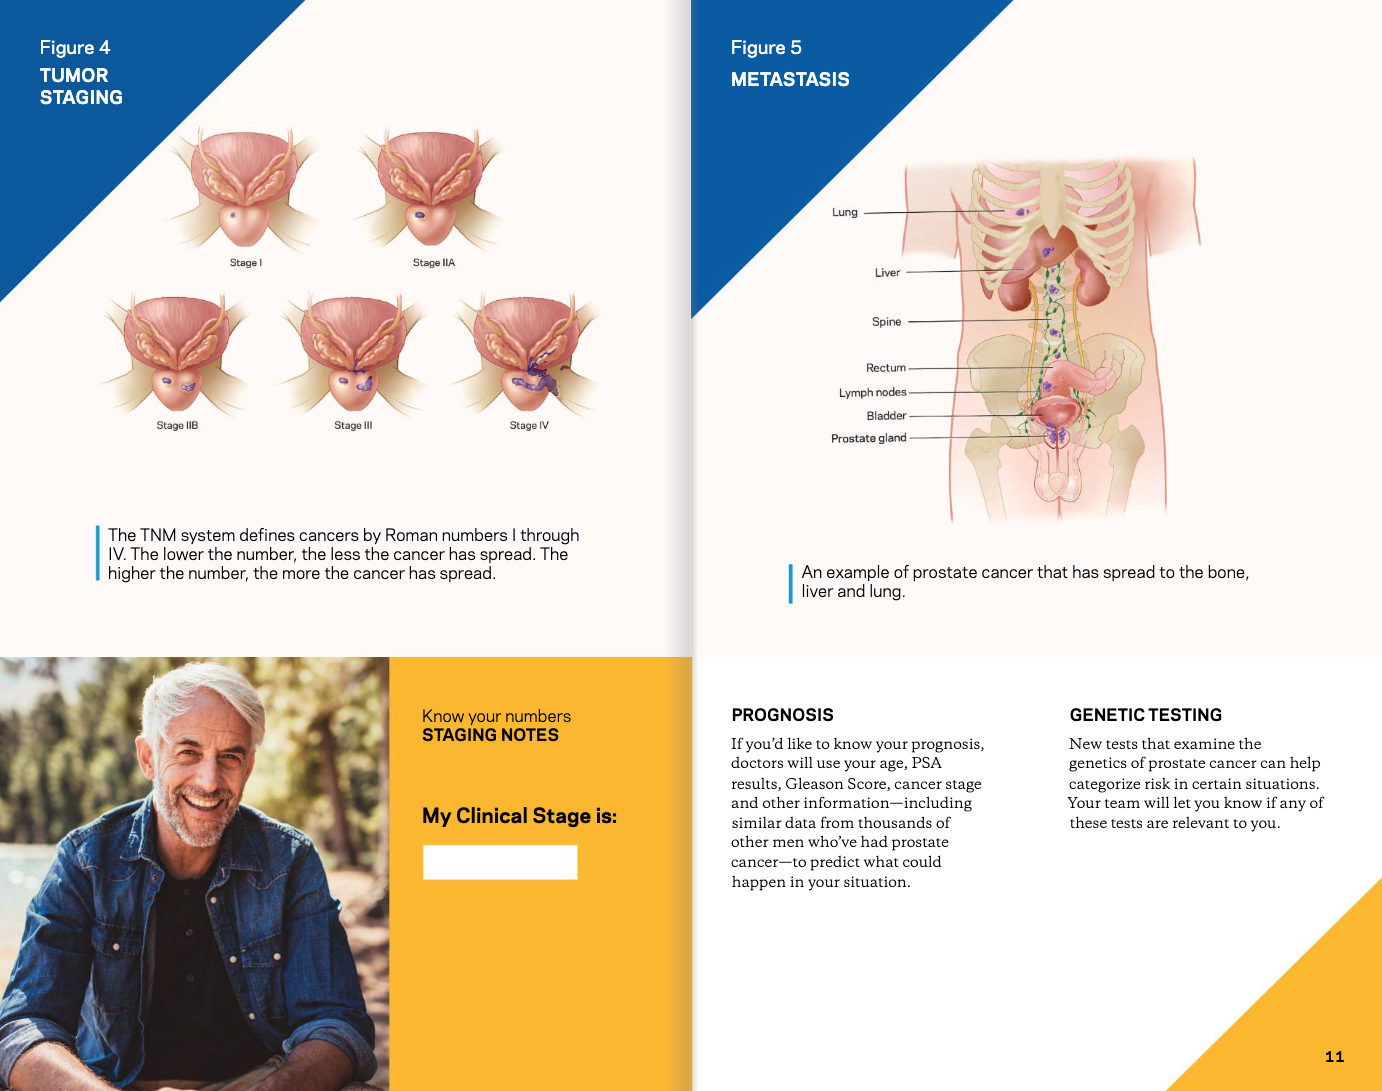

Informative, straightforward illustrations can help patients better understand their medical condition, treatments and procedures. Doctors and healthcare providers can use illustrations to communicate more effectively and reduce a patient’s anxiety about their condition or treatment.

Prostate Cancer Booklet

Created clear, accurate, and visually engaging medical illustrations for a patient education booklet on prostate cancer for a hospital system. The illustrations simplified complex anatomical and clinical concepts, helping patients better understand diagnosis, treatment options, and disease progression.

Client: Northwell Hospital System

Patient Education: Prostate Cancer